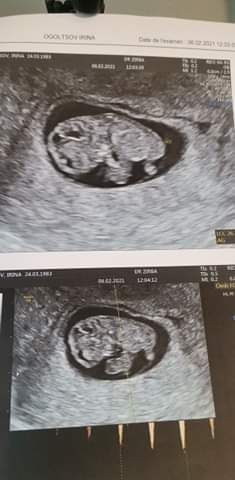

Иринка следующая будет дочка

Посмотрите кто у нас будет? Оба узи, разница в 4 недели трансвагинально

30.03.2021